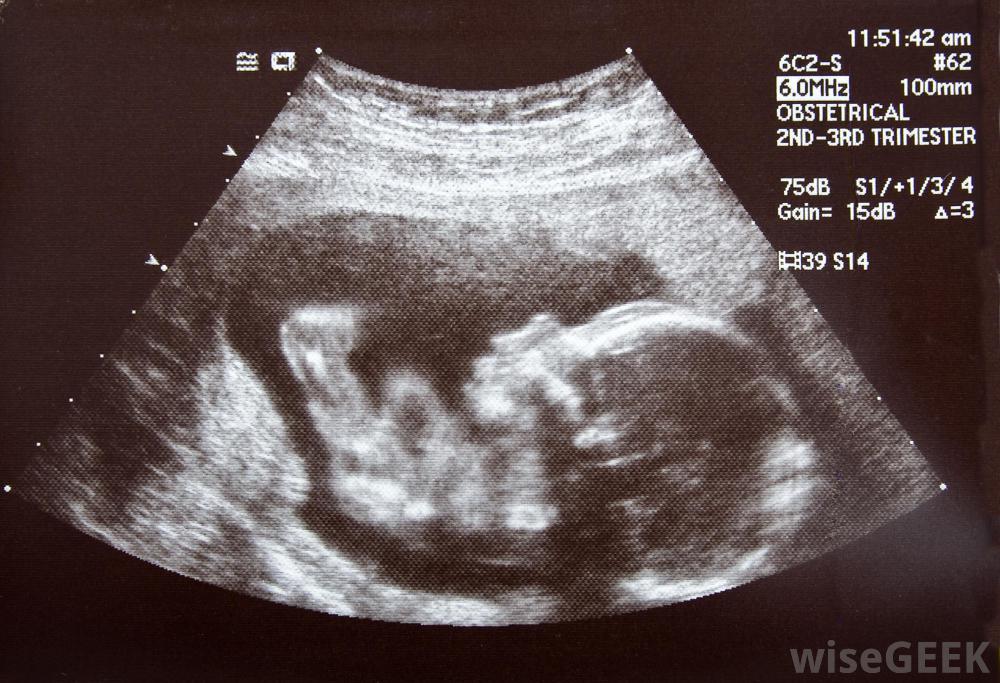

胎儿缺氧可能发生在健康、顺利的怀孕之后。